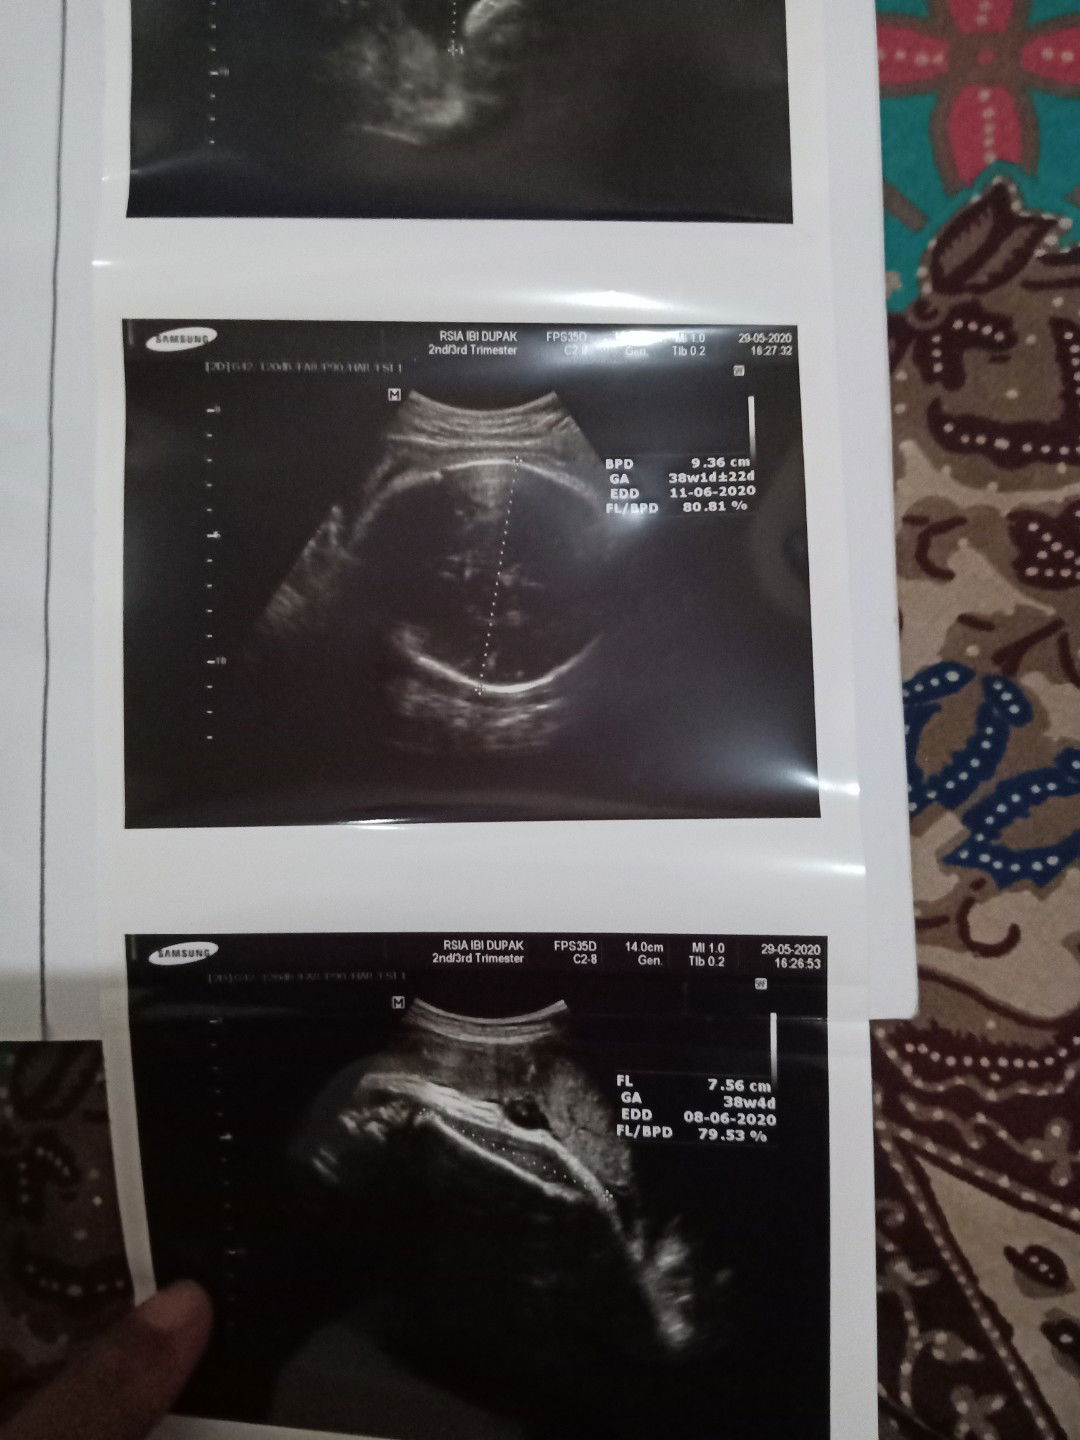

Hpl awalnya 14juni jd maju 8juni, di tap aslinya 37w tp td usg 38w kok bingung ya saya bun hehe ga sabar pingin cepet2 lahiran bun bagi tips induksi alami dong bun